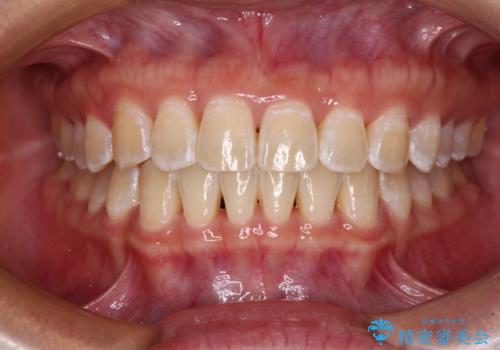

- 上下前歯の叢生と八重歯を気にして来院された患者様です。

前歯部叢生のスペースを獲得するため、上下顎左右小臼歯各1歯を抜歯することとしました。

歯列はきれいに整いますが、歯肉ラインは治療前の歯肉の位置を踏襲します。

特に八重歯であった歯は歯冠が長く見えますので、改善を希望される場合には、歯肉移植術を行う必要があります。